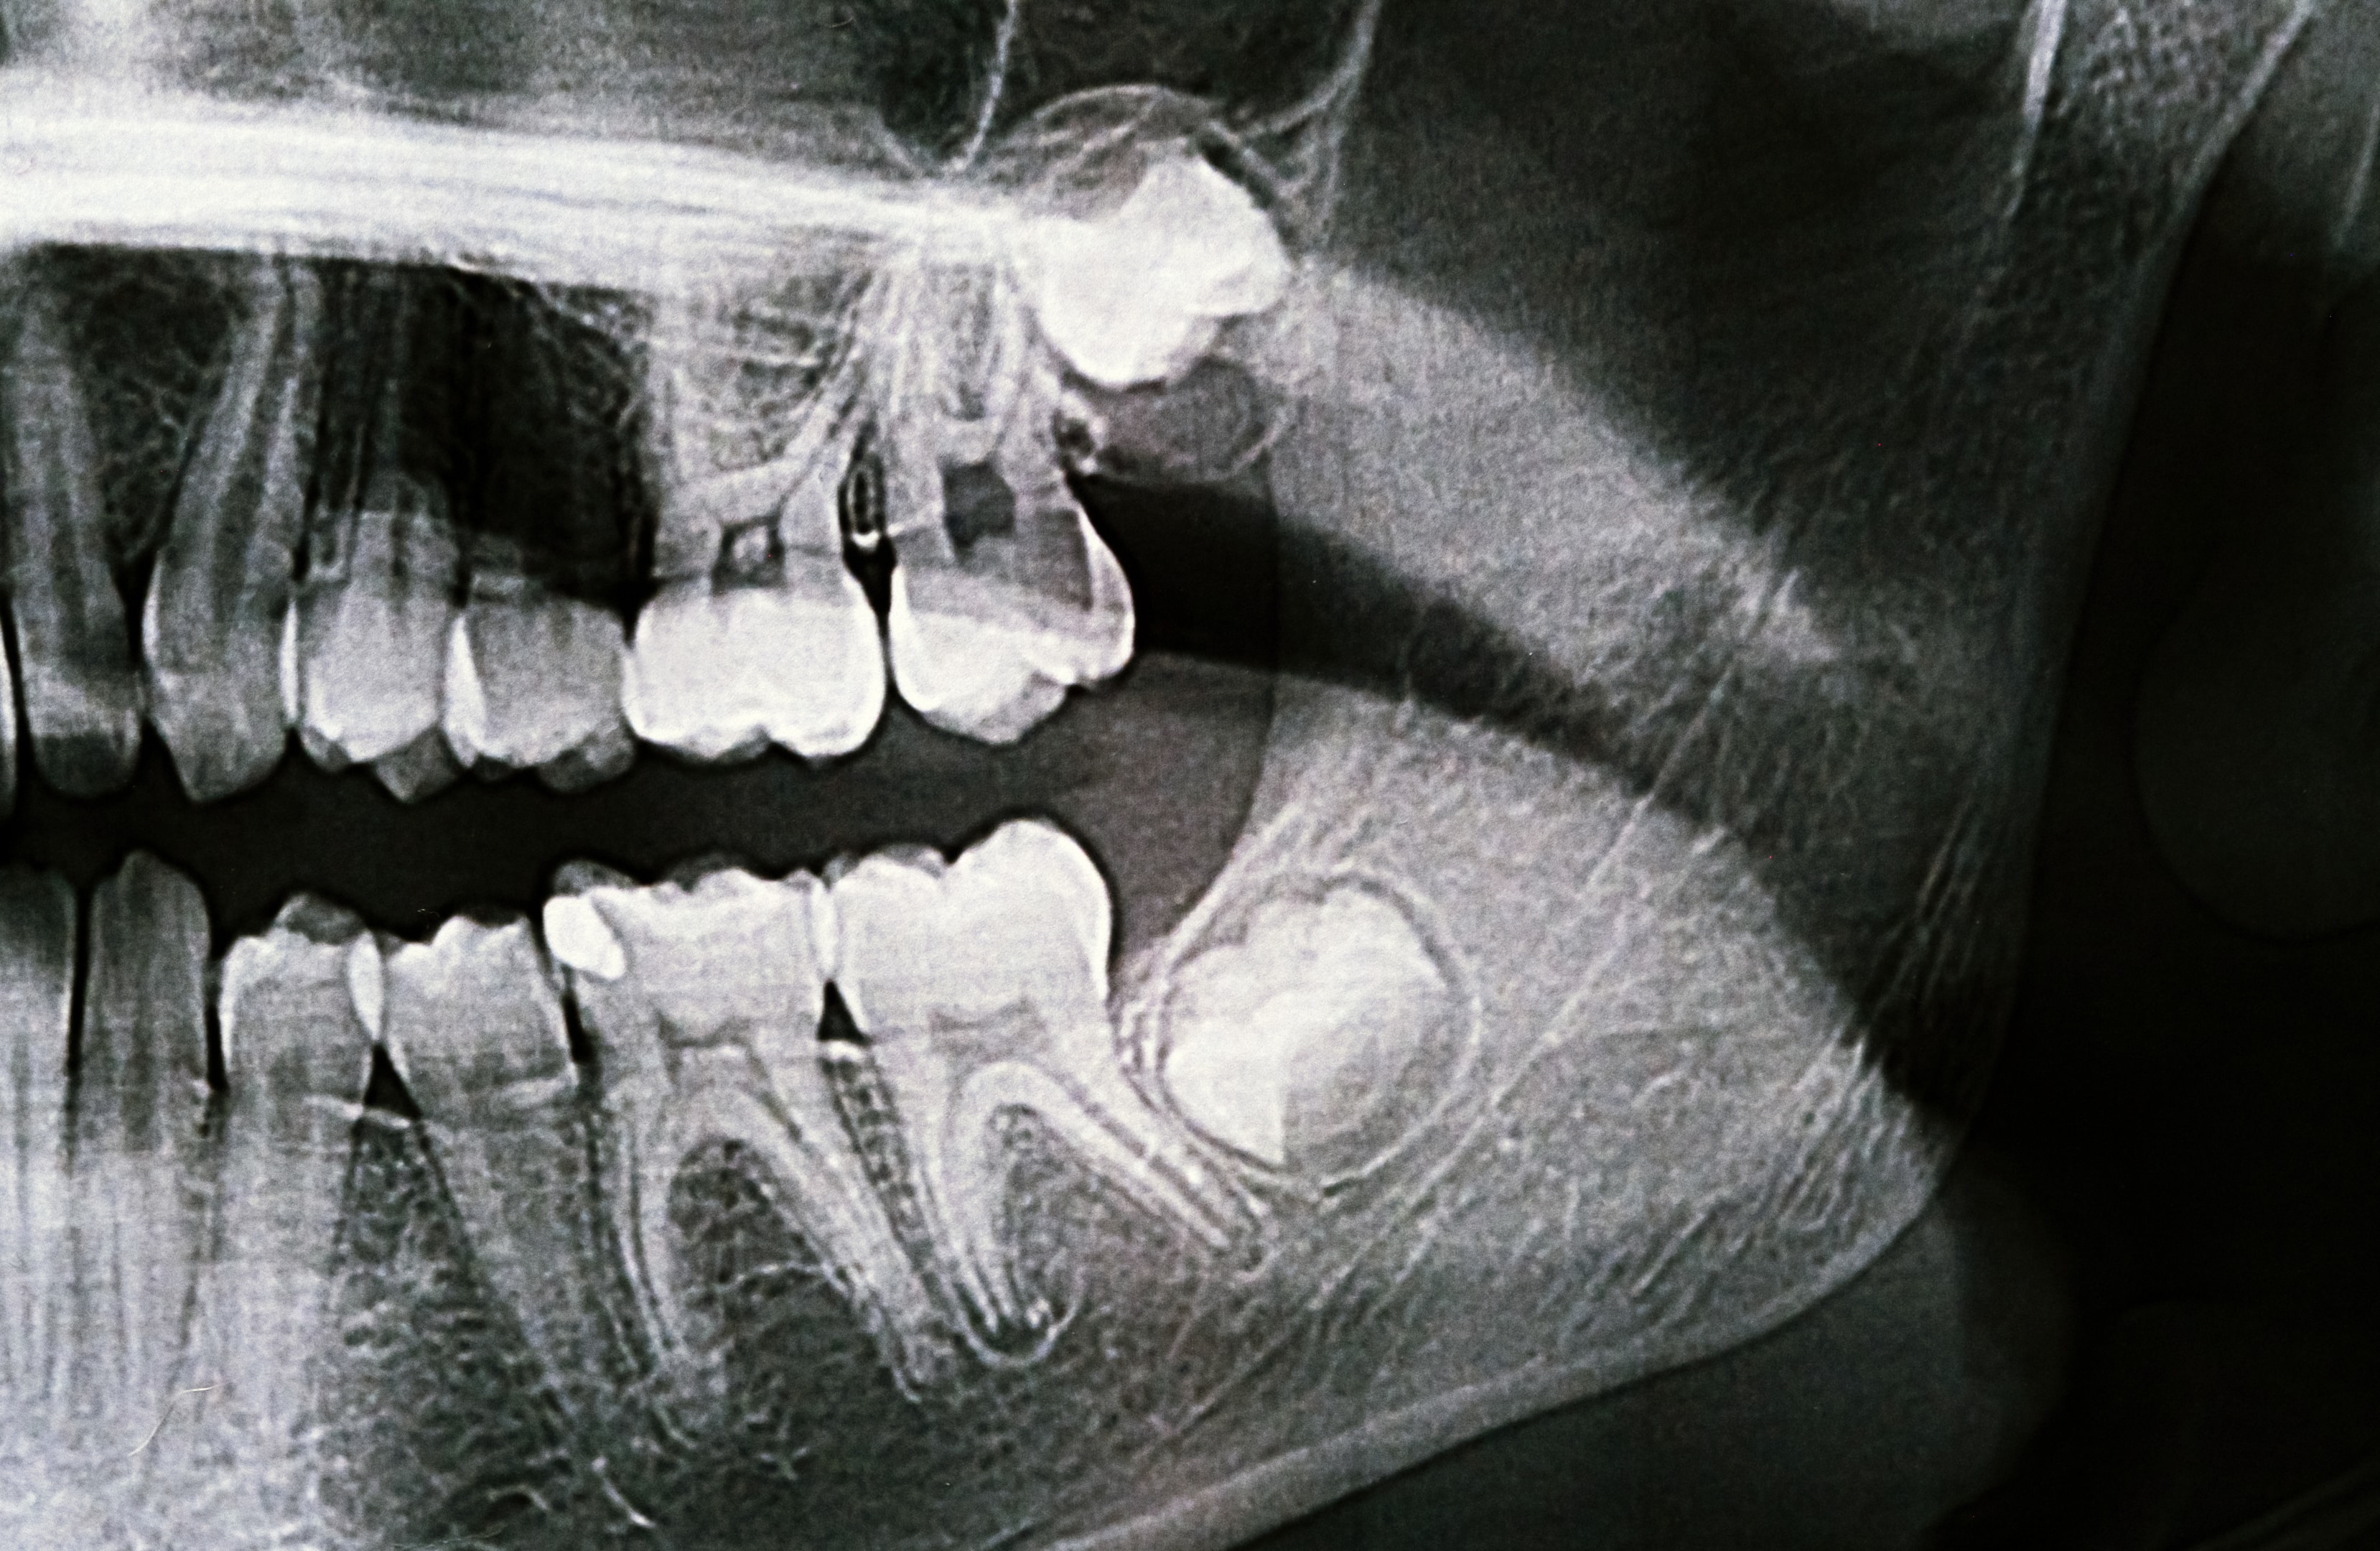

You might think of a decayed tooth as just a local problem, but the pain and infection associated with it can easily spread or be "referred" to other areas. Your head, face, and jaw are all closely linked by a complex network of nerves. When a tooth is decayed, especially if it's severe, it irritates these nerves, sending pain signals that your brain can interpret as a headache.

Think of it like a ripple effect. A small issue in one area can create much larger waves of discomfort throughout your body. This is particularly true for dental issues, as the trigeminal nerve, which supplies sensation to your face and controls chewing muscles, is directly involved. When this nerve is irritated by a decayed tooth, headaches can become a very real and often debilitating symptom.

- Inflammation and Infection: When decay reaches the pulp (the innermost part of the tooth containing nerves and blood vessels), it can cause inflammation (pulpitis) or even an infection leading to an abscess. This inflammation or infection puts pressure on surrounding nerves, and the pain can radiate upwards to your head.

- Referred Pain: Our brains can sometimes get confused about where pain is coming from. Pain originating in a decayed tooth can be "referred" to other areas of the head, such as the temples, forehead, or even around the eye. This means the actual source of the pain is the tooth, but you feel it elsewhere.